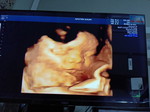

Bunda izin tanya, skarang kandungan saya masuk 8 minggu tapi saya udh gk mual apa normal? Msih gampang capek, PD nyeri, gk mood makan (harus dipaksa) tpi mual saya udh berkurang jauh dari sebelumnya, ini gpp kan ya bund? Waktu kehamilan pertama dlu, saya keguguran jdi saya blum banyak tau bund🙏 #mohonbantujawabbunda #Sharingdong_Bund #bantujawab #firstmom #Needadvice

Bund kira" setelah rujukan pertama kapan ya boleh minta rujukan lagi? Jadi aku Desember minta rujukan buat periksa kehamilan tpi qodarullah keguguran dan harus kuret. Dokter bilang boleh hamil setelah 3x siklus haid, tapi Bru haid 1x aku udh positif lagi sekarang. Nah pertanyaannya kapan bisa minta rujukan lgi dari faskes 1 buat USG dan cek kandungan ya bund? Apa harus nunggu minimal 3 bulan dari rujukan awal atau udh bisa minta lagi skarang ya? Soalnya mengingat aku riwayat keguguran ditambah hamil jga lebih cepat dari anjuran dokter tuh takutnya lebih beresiko aja gtu bund. Aku emang udh periksa tapi bukan d dokter yg sblumnya nanganin aku jdi Kya kurang enak buat ngobrolnya #mohonbantujawabbunda #Sharingdong_Bund #bantujawab